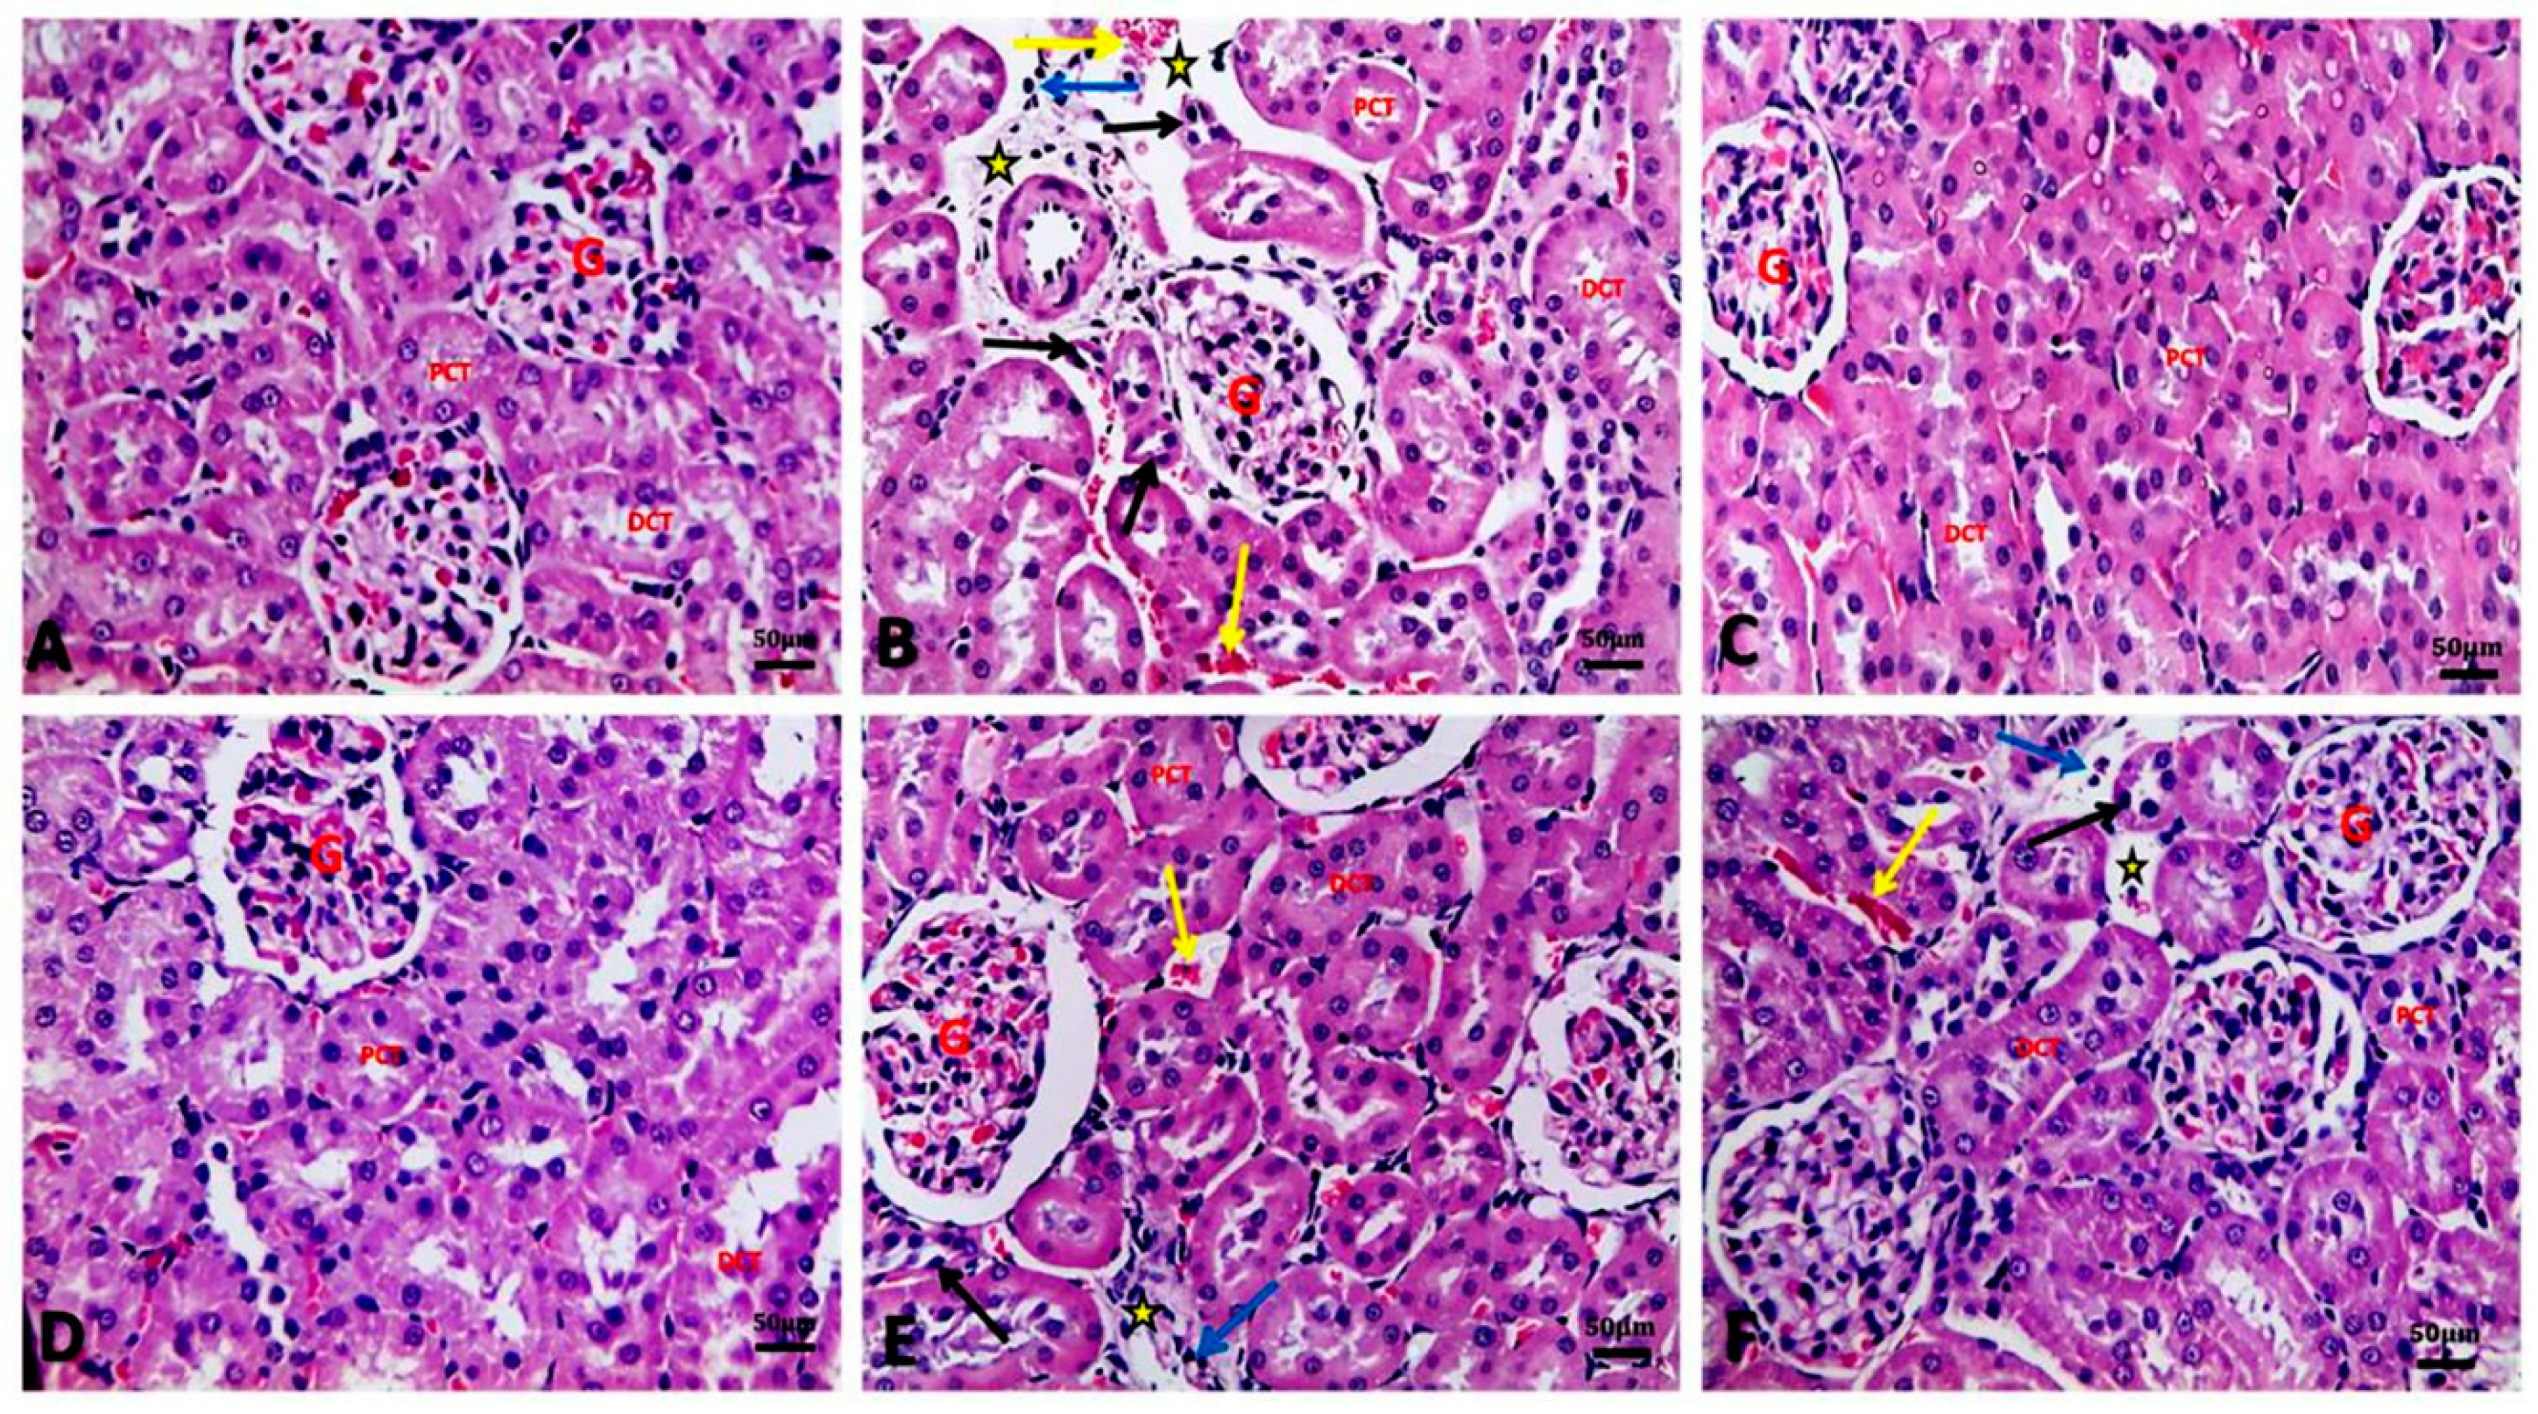

3.6. Argan Oil Ameliorated Betamethasone-Induced Alterations in Renal Histoarchitecture of Rats